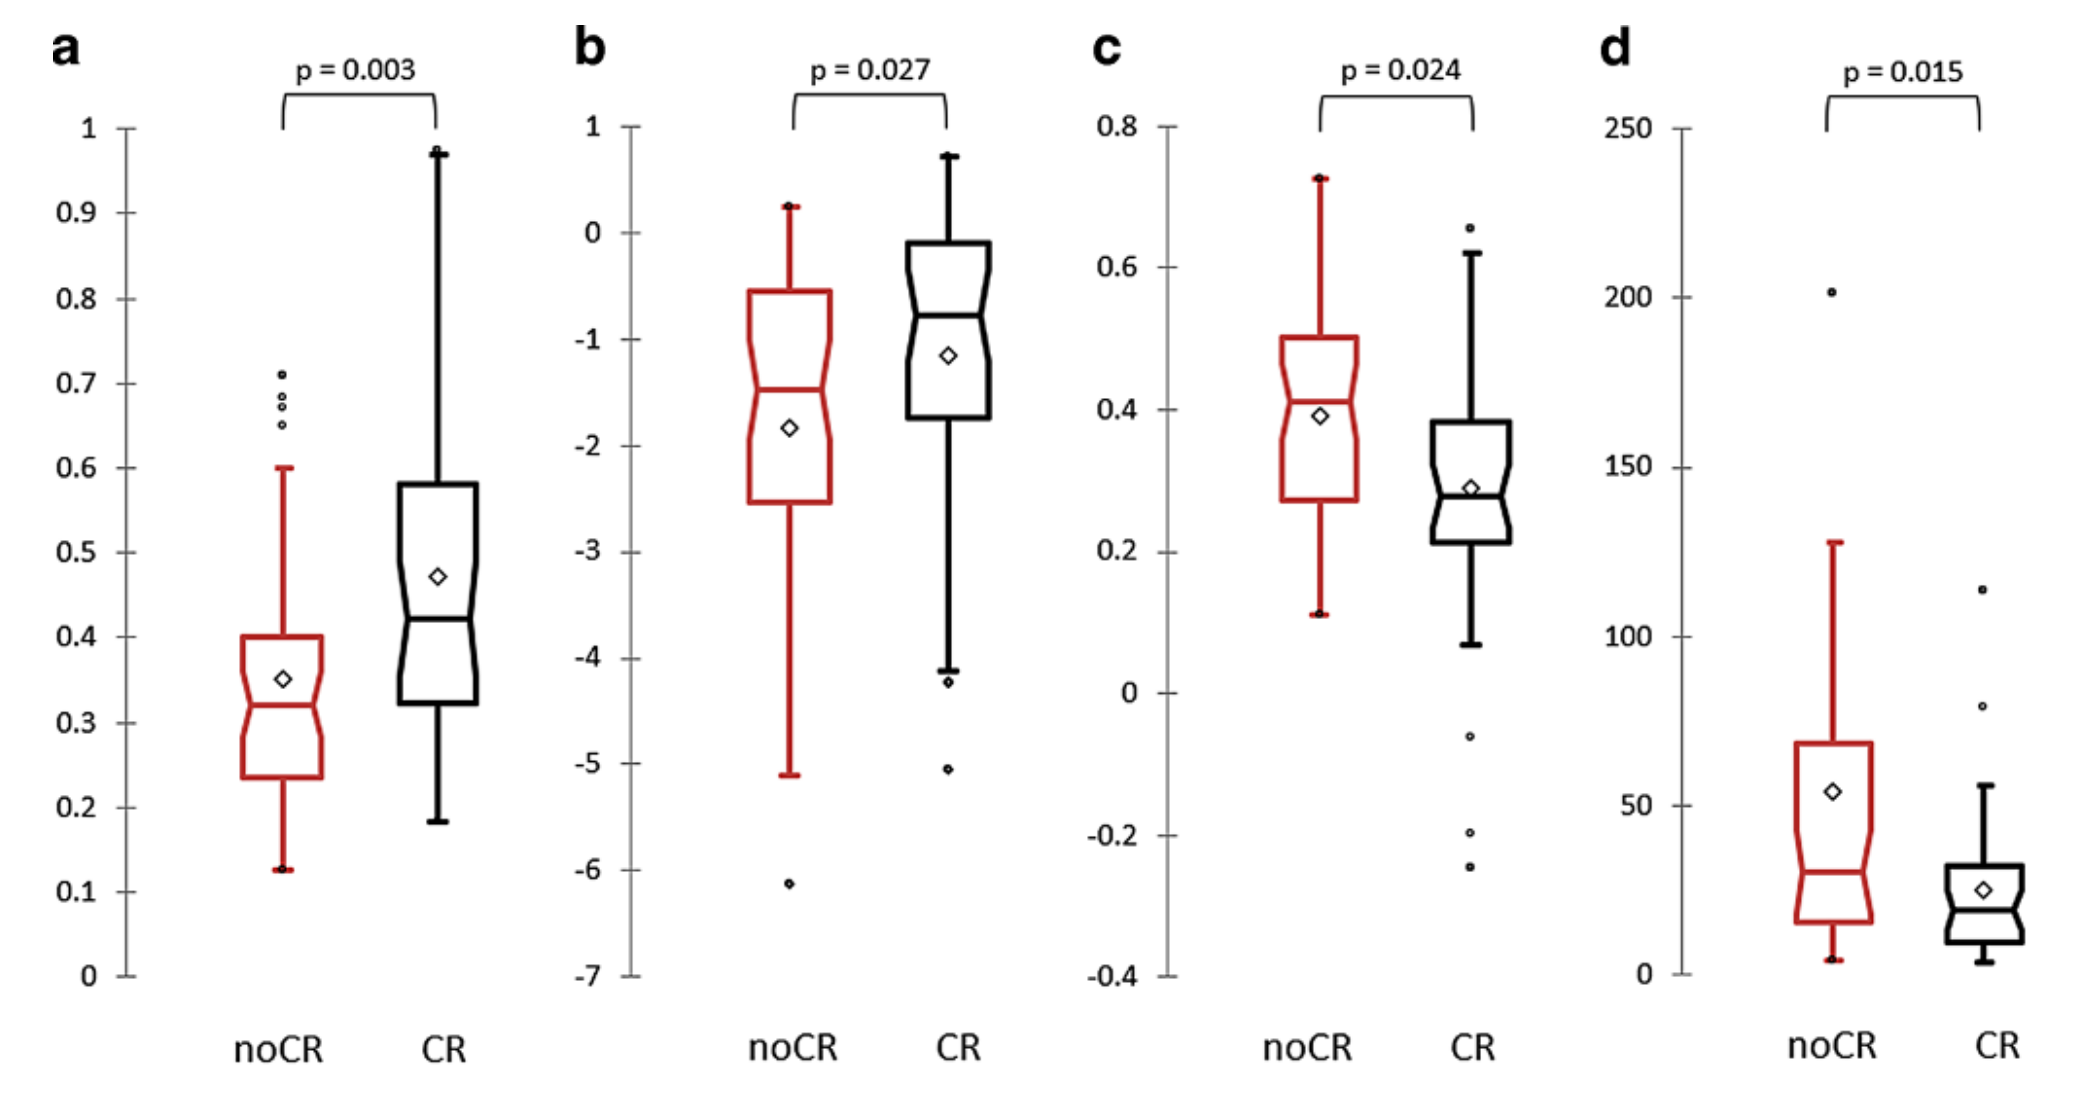

Fig. 1 展示了四个与治疗反应结果相关联的放射组学特征的箱形图(Box-and-whisker plots),这些特征在单变量分析中与完全缓解(CR)和非完全缓解(noCR)相关。每个箱形图代表了一个特定的放射组学特征,并且比较了CR组和noCR组之间的差异。以下是对这些图表的分析:

-

表面体积比率 (Surface Volume Ratio, SVR):

- 箱形图a展示了表面体积比率的分布情况。

- SVR是一个描述肿瘤形状的放射组学特征,较高的SVR值表明肿瘤具有更不规则的边缘。

-

偏度 (Skewness, Skew):

- 箱形图b展示了偏度的分布情况。

- 偏度是衡量数据分布不对称性的统计量,正偏度表示数据分布的尾部向右延伸,负偏度则向左延伸。

-

相关性 (Correlation, Corr):

- 箱形图c展示了相关性的分布情况。

- 相关性是衡量肿瘤内部结构均匀性的指标,高相关性表明肿瘤内部的像素强度值更加一致。

-

灰度非均匀性 (Grey Level Nonuniformity, GLNU):

- 箱形图d展示了灰度非均匀性的分布情况。

- 灰度非均匀性是衡量图像中灰度分布不均匀性的指标,较高的值表明肿瘤内部的灰度变化更大。

每个箱形图通常包含以下元素:

- 中位数 (Median): 箱形图中的中线表示数据的中位数。

- 上四分位数 (Upper Quartile): 箱子的上边缘表示数据的上四分位数(75%分位数)。

- 下四分位数 (Lower Quartile): 箱子的下边缘表示数据的下四分位数(25%分位数)。

- 异常值 (Outliers): 箱子外的点通常被认为是异常值。

通过比较CR组和noCR组的箱形图,研究人员可以评估这些放射组学特征是否能够区分两种不同的治疗反应。如果CR组和noCR组的箱形图有显著差异,这可能表明相应的放射组学特征对于预测治疗反应具有潜在的预测价值。例如,如果CR组的SVR值普遍高于noCR组,这可能表明具有较高SVR值的肿瘤更有可能在SBRT治疗后实现完全缓解。

需要注意的是,为了确定这些放射组学特征的预测价值,研究人员还会进行统计测试(如Mann–Whitney U test),以评估两组之间的差异是否具有统计学意义。

尽管没有任何临床特征预示着完全缓解,我们发现四个放射组学特征(表面体积比、偏度、相关性和灰度非均匀性)与完全缓解显著相关,突出了放射组学分析在预测SBRT治疗后肺部转移瘤结果方面的潜力。

表面体积比是形状特征中与完全缓解相关性最高的。特别是,我们发现SVR值较高的病变在SBRT后有更高的完全缓解概率。这并不令人意外,因为已有充分报道指出,体积较大且不规则的肿瘤在总体生存和局部控制方面预后较差。有趣的是,偏度和相关性也在之前的放射组学研究中被确定为肺肿瘤的主要放射组学特征。

据我们所知,只有一项由Cheung等人[24]进行的研究评估了放射组学在预测SBRT治疗后肺寡转移瘤反应方面的作用。作者报告说,偏度和均方根是放射学治疗反应的预测因子,准确率为74.8%。另一方面,一些研究专注于将放射组学应用于原发性肺癌,以识别预测放射组学特征。例如,Bousabarah等人[22]报告了CT放射组学分析在110例不可手术的早期NSCLC患者中的应用,这些患者接受了SBRT治疗,旨在预测局部控制、总体生存和无病生存。具体来说,作者报告说,具有高偏度(即Hounsfield值较低的病变占主导地位)的肺肿瘤局部失败的风险较低,生存概率较高,而具有高相关性(组织同质性的度量)的肺肿瘤更可能导致局部失败。这些结果与我们发现的完全一致。